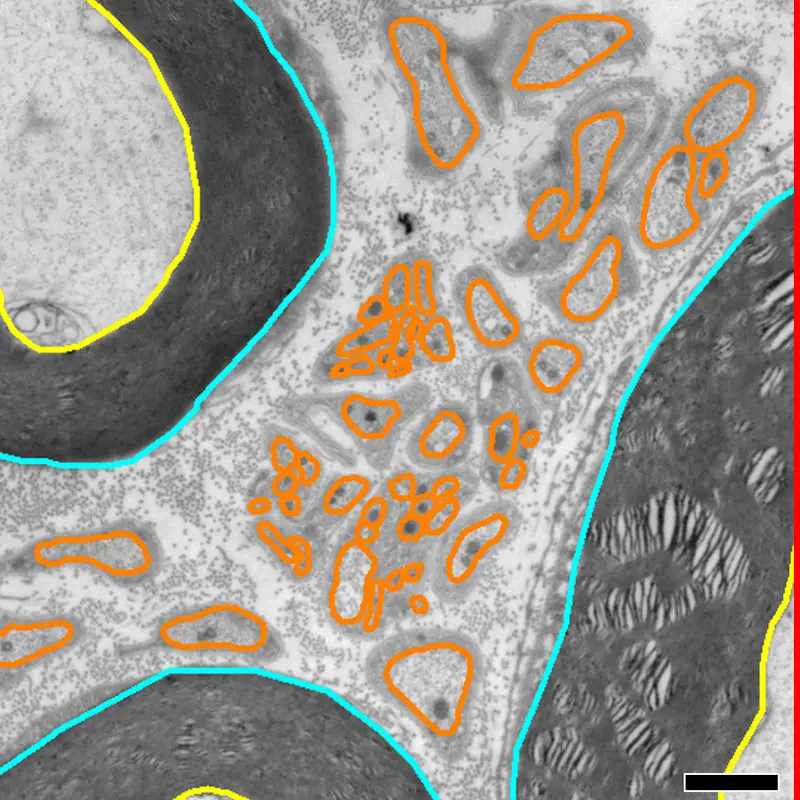

Outer and inner borders of myelinated axons shown in light blue and yellow, respectively; outline of unmyelinated axons is contoured in orange. Digital measurements of nerve fiber area and perimeter from each axon are used to determine a corrected value of fiber size based on SAE approach. Scale: 1 µm

Segmentation of axons in light and electron micrographs allows for quantitative high-resolution analysis of nerve fiber tissues—but varied axonal angles result in an overestimation of fiber sizes. The SAE approach today corrects for size and myelination of individual nerve fibers for light and electron microscopy by compensating for the shape and dispersion angle of individual nerve fibers.

The correction for fiber dispersion angle markedly reduces the number of outliers and data scatter, allowing for enhanced anatomical mapping as well as improved predictions of functional properties in translational studies of neural repair and nerve regeneration.

The SAE approach was validated by light and electron microscopy against the traditional methods of determining nerve fiber size and myelination—which had resulted in significant overestimations of fiber diameters.